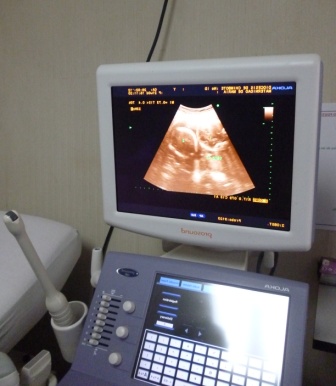

Chimbotenlinea.com(Redacción central).-El Centro de Obras Sociales, Maternidad de María, cuenta con dos modernos equipos ecógrafos y brinda este servicio a la comunidad con la garantía de que los exámenes son realizados por médicos de reconocida trayectoria en nuestra localidad. Estos equipos son muy útiles ya que ayuda la detección de enfermedades, entre ellas el temido cáncer.

Este servicio es muy acogido en la Maternidad de María por su bajo costo, su implementación de última generación y el excelente personal profesional; las ecografías 3D y 4D son muy requeridas por las madres gestantes, ecografías transvaginales y examen de mamas, entre otras.

Este equipo cuenta con un transductor o sonda conectado a un monitor por un cable. El transductor o sonda es un dispositivo parecido a un micrófono.

El radiólogo administra un gel sobre la zona a explorar y aplicará la sonda sobre la piel. La imagen aparece inmediatamente en la pantalla. A veces la propia paciente puede ver el monitor.